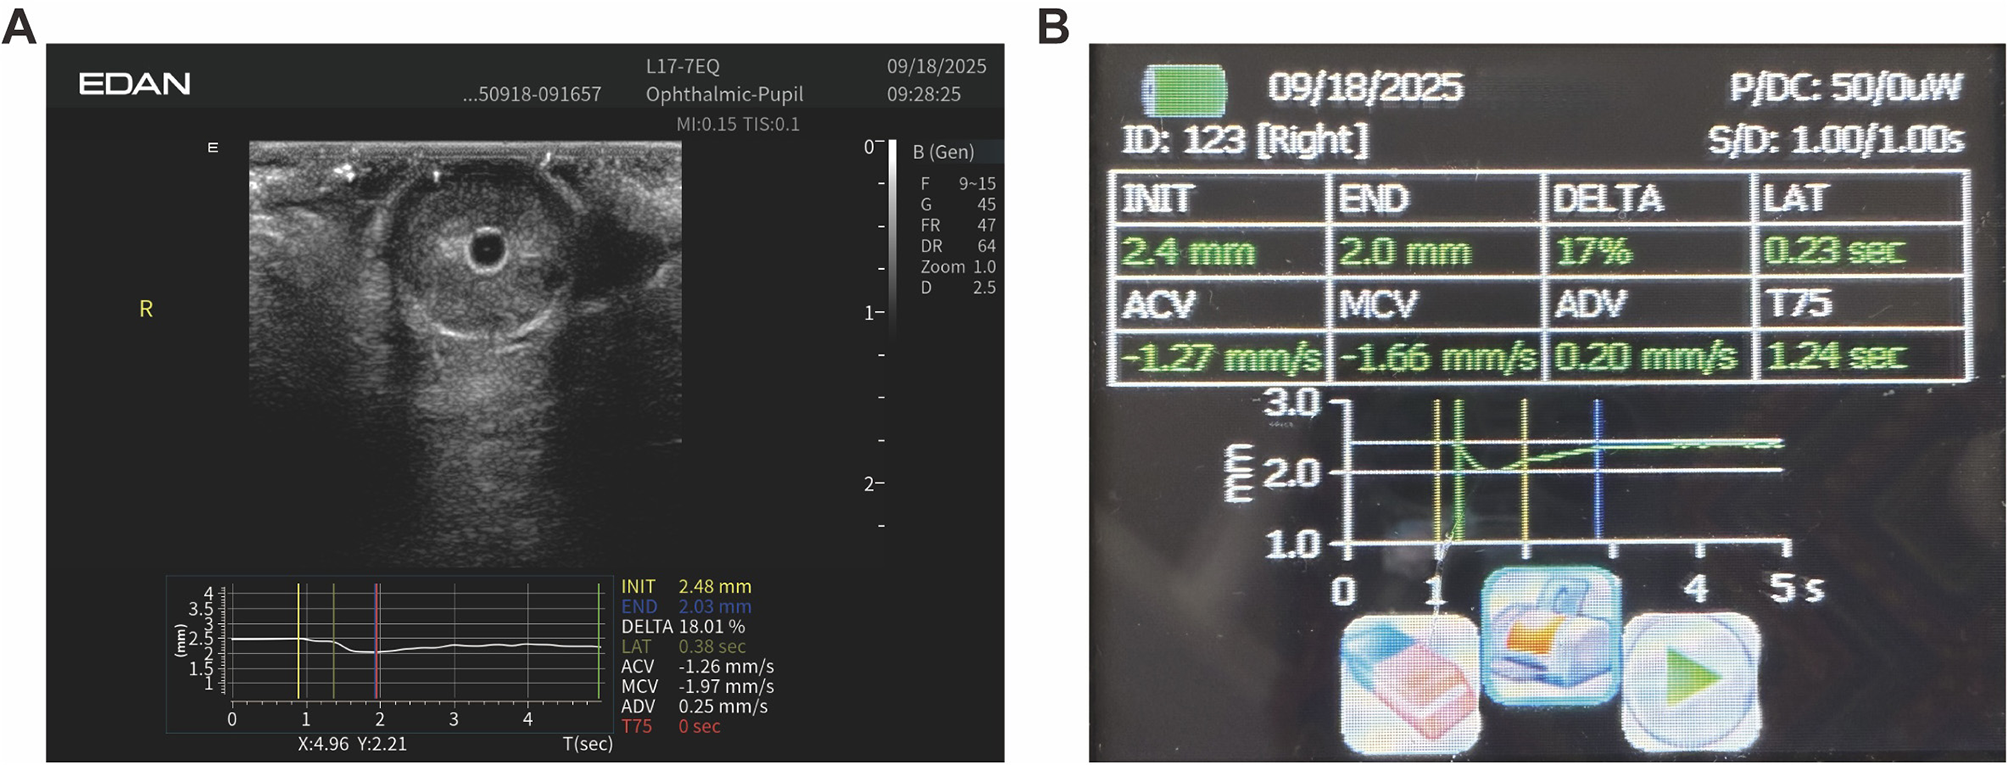

Figure 1

Automated ultrasound pupillometry system. (A) Handheld linear ocular probe (L17–7EQ) used for transpalpebral imaging. (B) EDAN AX8 ultrasound system in the “Ophthalmic-Pupil” preset, displaying the B-mode ocular image. (C) Auto-UPA pupillometry mode with the integrated light source activated, ready for automated pupillary light reflex acquisition.

The Auto-UPA algorithm processed each B-mode cine loop through a standardized pipeline. First, a short pupillary cine sequence was acquired under fixed depth and gain settings. Second, the pupil region of interest was automatically localized using intensity-based thresholding and edge detection, followed by morphological filtering to segment a smooth pupil boundary. Third, pupil diameter was computed frame by frame as the maximal horizontal chord through the pupil centroid, generating a continuous diameter–time curve aligned to the onset of the light stimulus. Finally, key PLR metrics were automatically derived and exported for analysis, including initial diameter (INIT), end constriction diameter (END), constriction ratio (DELTA = [INIT – END]/INIT), latency (LAT; time from light onset to the onset of constriction), average constriction velocity (ACV), and average dilation velocity (ADV). On-screen quality-control prompts verified adequate signal acquisition (Figure 4A).

Figure 4

Representative Auto-UPA acquisition and on-screen output. (A) B-mode ocular image with overlaid time–diameter trace and automatically derived pupillary light reflex metrics, including initial diameter (INIT), end diameter (END), constriction ratio (DELTA), latency (LAT), average constriction velocity (ACV), and average dilation velocity (ADV). (B) Corresponding Auto-UPA summary screen for the same eye, displaying the numerical values of PLR metrics in a tabular format.

IPA was conducted immediately after Auto-UPA using a standard monocular infrared pupillometer. The device was carefully positioned over the open eye, and a calibrated light stimulus was applied trans-corneally to elicit the PLR. All key parameters were automatically calculated by the device using its proprietary algorithms to align with the Auto-UPA output for direct comparison (Figure 4B).